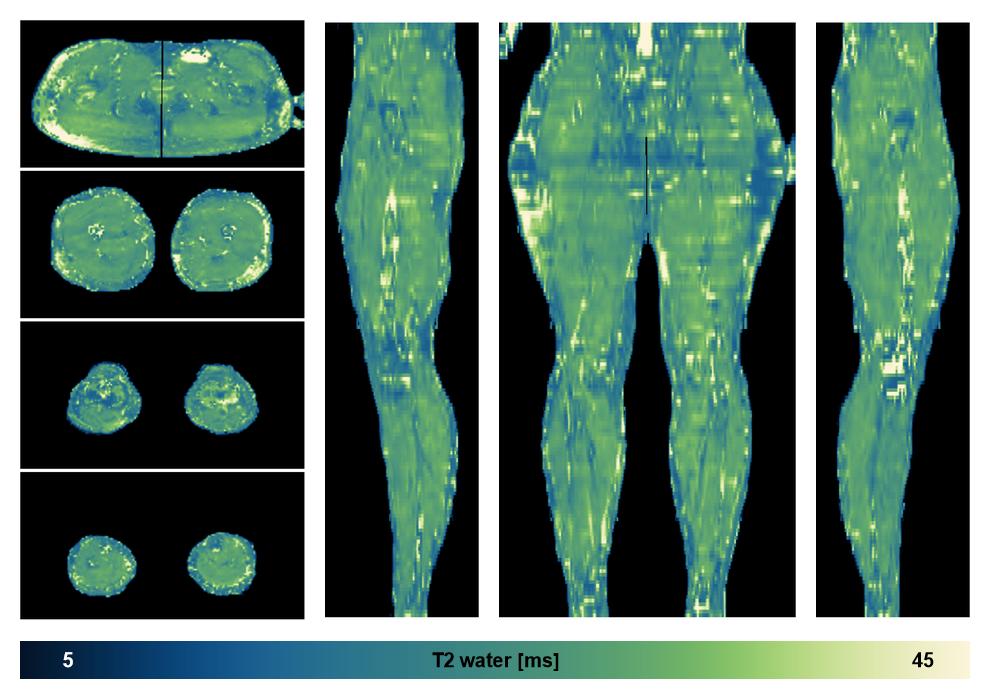

Water only T2 mapping

Multi echo spin echo T2 relaxation time mapping with EPG reconstruction, for information look here».

• Water only signal

The water part of the acquired multi-echo spin echo data.

• Water only T2 relaxation time

The water only T2 relaxation time of the lower extremity obtained from multi echo spin echo t2 mapping with EPG based reconstruction.